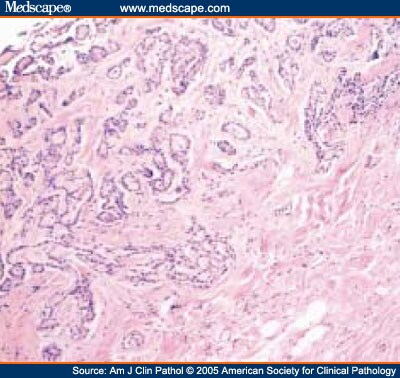

Peritoneal mesothelioma development and top treatments. Peritoneal mesothelioma patients may be given a combination of alimta and cisplatin, the same treatment given to pleural patients. In 2009, a patient went in for an unrelated procedure and signs of peritoneal mesothelioma were found. The patient was given a combination of alimta (500 mg) and cisplatin (80 mg). Peritoneal mesothelioma treatment, prognosis & diagnosis. Peritoneal mesothelioma is a cancer found in the peritoneum, a thin membrane surrounding the abdomen. Peritoneal mesothelioma is the second most common form of the disease, accounting for about 15 20% of all diagnoses. The prognosis is generally poor, though more favorable than other forms of. Pathology outlines p63. · encodes at least 6 different proteins with different biologic functions appears to regulate growth and development of epithelial organs (j biomed biotechnol 2011;2011864904), as germline mutations cause ectrodactyly (missing or irregular fingers or toes), ectodermal dysplasia and facial clefts syndrome, also called limb mammary syndrome (hypoplasia / aplasia of mammary glands. Peritoneal mesothelioma treatment, prognosis & diagnosis. Peritoneal mesothelioma is a rare type of cancer that occurs in the thin cell walls which surround the abdominal cavity, known as the peritoneum and is caused by asbestos exposure. Peritoneal mesothelioma mesothelioma resource online. Peritoneal mesothelioma peritoneal mesothelioma is the secondmost common type of mesothelioma, occurring in about 20% of cases. This form of mesothelioma is a cancer that occurs in the peritoneum, or the lining of the abdominal cavity. The peritoneum surrounds the internal organs for support and lubrication.

Peritoneal mesothelioma causes, stages, and treatment. Peritoneal mesothelioma has a long latency period. Several decades long, this is the time between exposure to asbestos and diagnosis of cancer. Though the asbestos fibers begin to do damage as soon as they enter the body, it takes many years for their impact to be felt and noticed. Vegetarian and vegan diets for cancer mesothelioma. A healthier diet for mesothelioma and cancer patients. All the reasons vegan and vegetarian diets reduce cancer risks, also make them good for cancer patients. What is mesothelioma and types of mesothelioma mesothelium info. Mesothelioma cancer develops from the linings of specific spaces or organs in the body, called the mesothelium. There are four key kinds of mesothelioma, such as malignant pleural mesothelioma, peritoneal mesothelioma, pericardial mesothelioma, and esophageal disease. Pleural mesothelioma entails tumors inside the pleura (lung linings). Stages of peritoneal mesothelioma early stage vs. Advanced. Quick summary. Peritoneal mesothelioma is an exceedingly rare diagnosis, with only around 500 new cases per year in the united states. Because it’s so rare and often isn’t diagnosed until it has reached significant metastasis (spreading), it’s difficult for specialists at this time to form an official peritoneal mesothelioma staging system. Peritoneal mesothelioma causes, treatment & survival rates. Peritoneal mesothelioma is a cancer that forms in the tissue lining of the abdomen (peritoneum). It is caused by ingesting asbestos. It is the secondmost common type of mesothelioma. Half of patients who elect surgery with heated chemotherapy live at least five years. Peritoneal mesothelioma is a. Peritoneal mesothelioma a review pubmed central (pmc). Peritoneal mesothelioma was first described in 1908 by miller and wynn. It is a rare neoplasm with a rapid fatal course (median survival 612 months, mean symptomstosurvival time 345 days). In the united states, the overall prevalence is 12 cases per million, with an estimated incidence of 200400 new cases annually.

Mesothelium wikipedia. The mesothelium is a membrane composed of simple squamous epithelium that forms the lining of several body cavities the pleura (thoracic cavity), peritoneum (abdominal cavity including the mesentery), mediastinum and pericardium (heart sac). Mesothelial tissue also surrounds the male internal reproductive organs (the tunica vaginalis testis) and covers the internal reproductive organs. What causes malignant mesothelioma? American cancer society. This may damage cells’ dna and cause changes that result in uncontrolled cell growth. If swallowed, these fibers can reach the abdominal lining, where they can have a role in causing peritoneal mesothelioma. But most people exposed to asbestos, even in large amounts, do not get mesothelioma. Malignant mesothelioma diagnosis, treatment and support. Peritoneal mesothelioma affects the protective lining of the abdominal cavity, the area of your body containing several organs, including the stomach, intestines, kidneys, and liver. It’s the second most common location where mesothelioma growsabout 20 to 24 percent of all mesotheliomas occur here. Peritoneal symptoms. Peritoneal mesothelioma cancer final stages flint law firm. Causes peritoneal mesothelioma can develop as a result of inhaling or ingesting asbestos fibers. Frequency peritoneal mesothelioma is the second most common form of asbestosrelated cancer. It accounts for 1520% of all mesothelioma cases, and nearly 500 people are diagnosed yearly with peritoneal mesothelioma in the united states. Mesothelioma & asbestos images, diagrams & graphs. Because it is so rare and caused by exposure to asbestos, mesothelioma is a complex topic. This series of charts and graphics make understanding the cancer easier, including how and where it develops, how susceptible the disease is and common locations for asbestos exposure. Someone i know has cancer macmillan cancer support. Someone i know has cancer. If your friend, relative, colleague or neighbour has cancer, it can be hard to know what to do for the best. We can help you find the right words and give you some tips to help you, because nobody should have to face cancer alone.